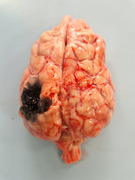

Brain metastases (BM) represent an unmet medical need in human medicine, and they are poorly documented in dogs. The aim of this multi-centre retrospective study was to report the clinical characteristics, primary solid cancer histology, advanced imaging findings, treatment modalities and potential prognostic factors in dogs with presumed BM that occurred either at the time of initial diagnosis or during follow-up. BM diagnosis was established through either imaging studies or histologic examination of specimens obtained during necropsy. A total of 58 client-owned dogs with histologically proven solid cancer and BM were included. Clinicopathologic variables, BM characteristics based on imaging and survival post-BM (SPBM) were recorded. Haemangiosarcoma (53.4%) and carcinoma (27.6%) were the most common primary tumour histotypes, followed by melanoma (12.1%) and undifferentiated sarcoma (6.9%). Synchronous BM and solitary BM occurred in 63.8% and 51.7% of dogs, respectively. The prosencephalus was most commonly affected, with 79% of dogs showing neurologic deficits. Antitumoural or palliative treatment was attempted in a minority of dogs, with no improved outcome. The median SPBM was 3 days (range, 1-255). The 3- and 6-month survival rates were 8.6% and 1.7%, respectively. Dogs with haemangiosarcoma (OR: 7.6; 95% CI, 2.2-25.8; p = 0.001) and those with distant metastases at presentation (OR: 16; 95% CI, 4.2-60.9; p < 0.001) had an increased likelihood of developing synchronous BM. Haemangiosarcoma and carcinoma were the tumours most frequently associated with BM, which were more commonly synchronous and symptomatic, with a high incidence of forebrain localization. The prognosis was poor, regardless of the primary cancer type.